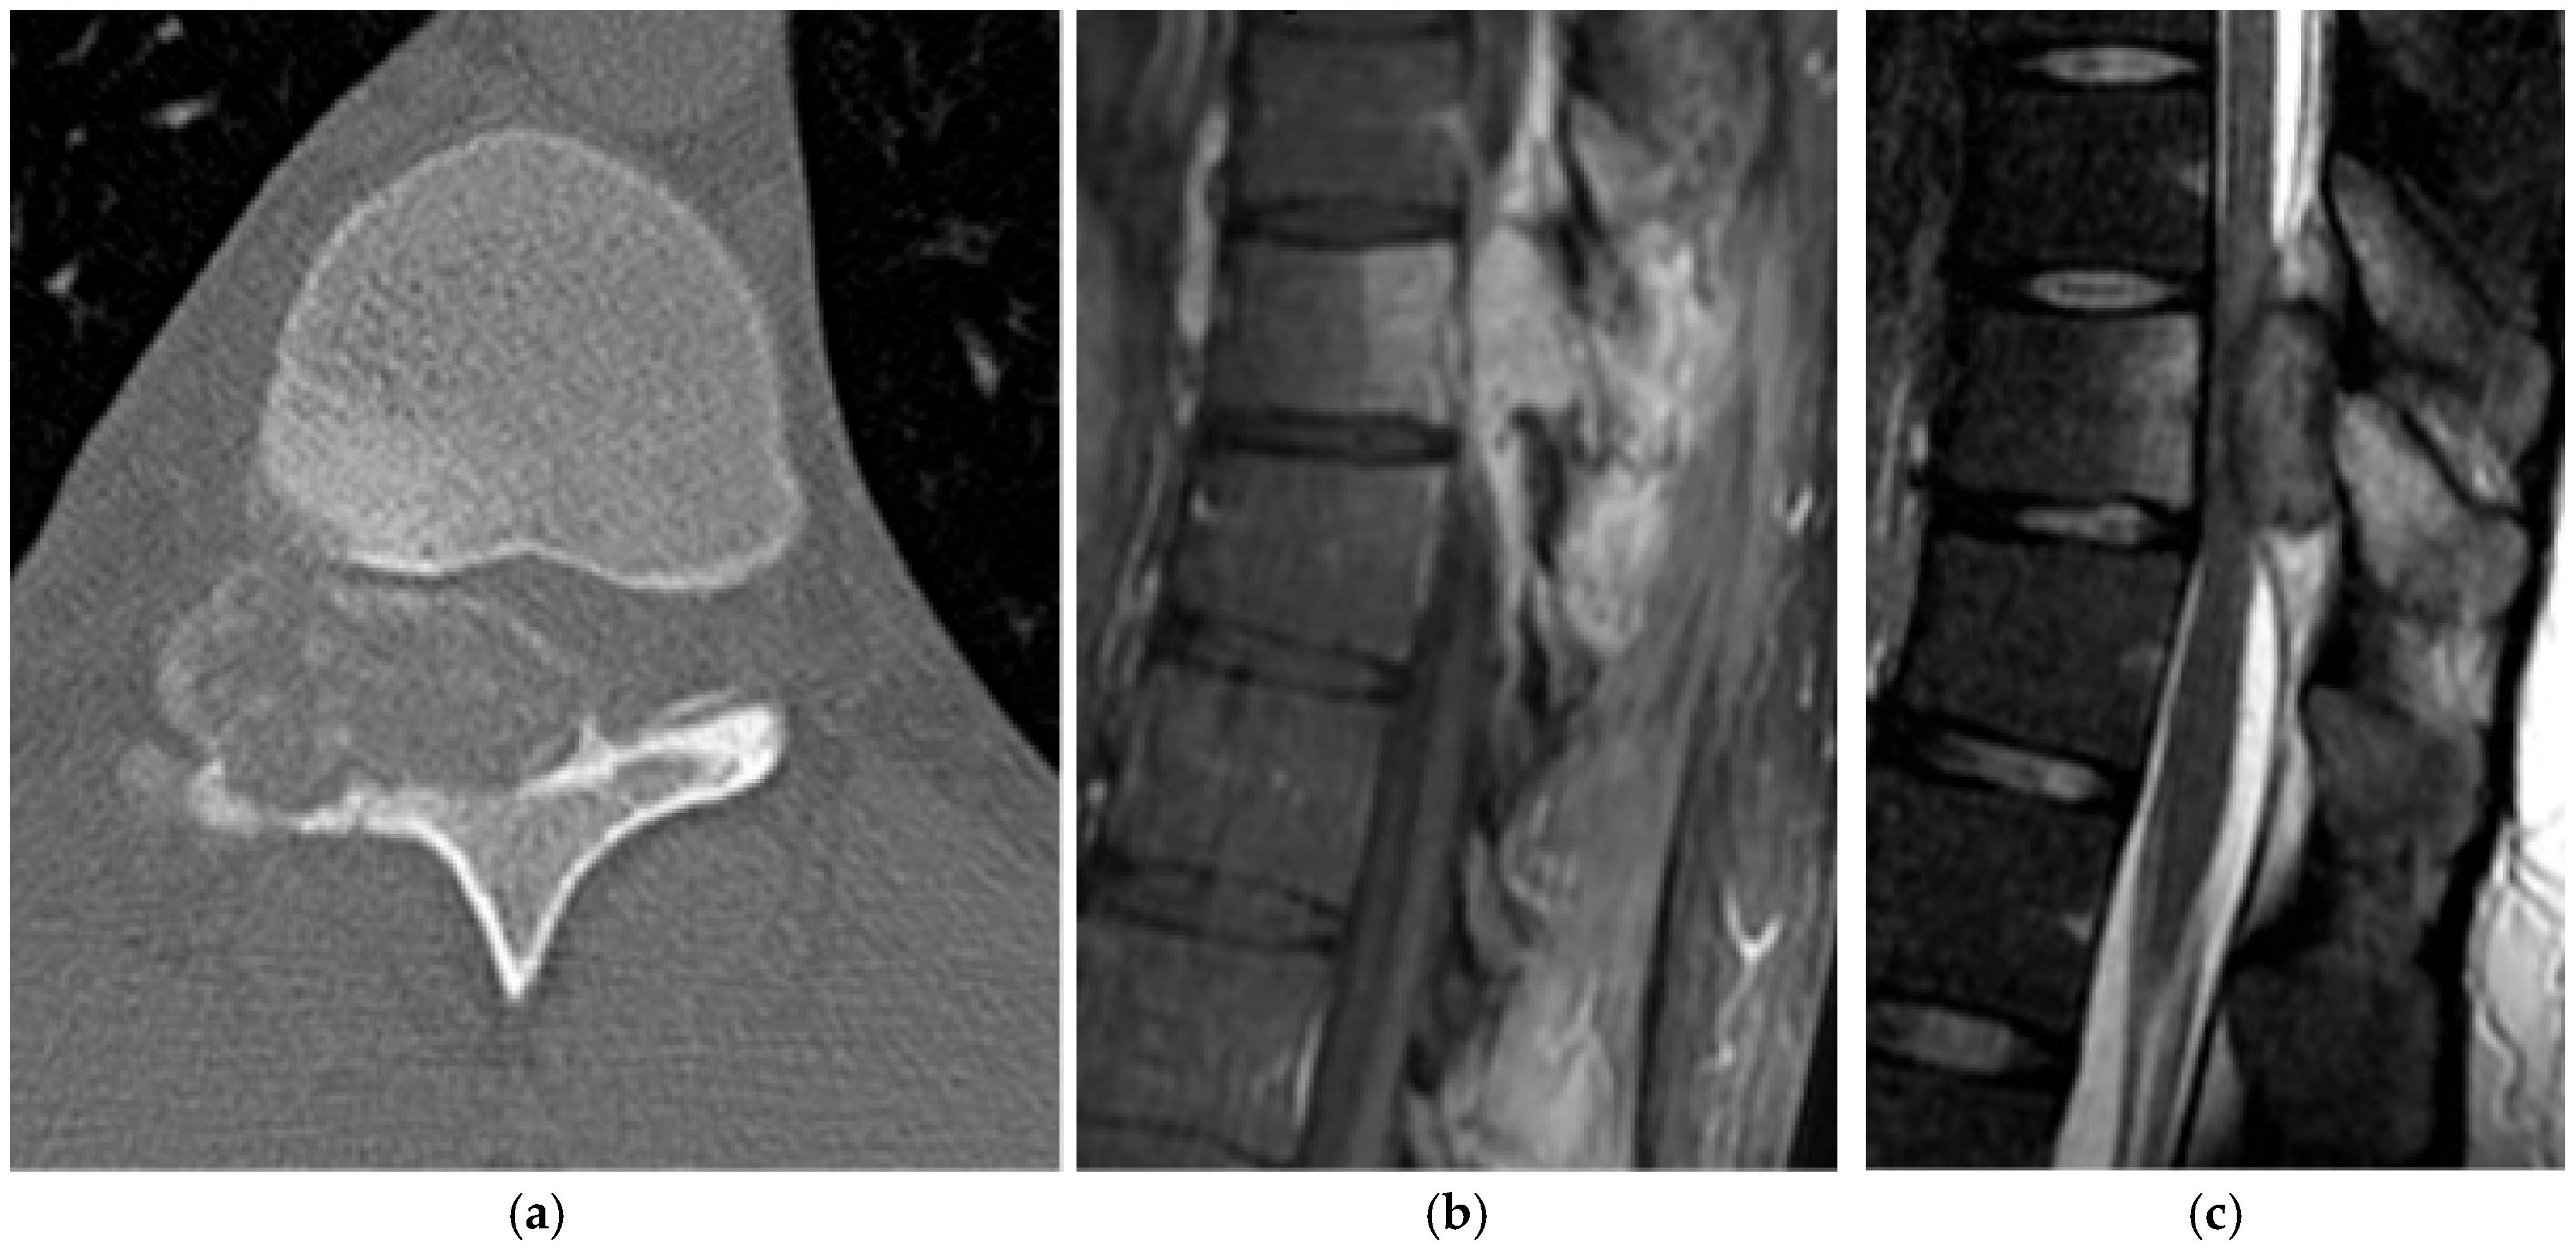

2.3.2. Chordoma

2.4. Hematolymphoid